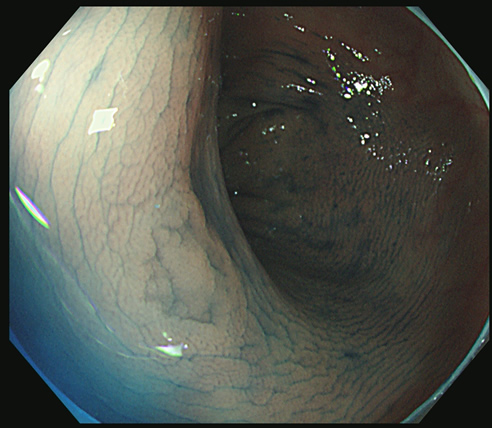

陥凹型過形成ポリープの完全切除

一方、陥凹型過形成ポリープは、頻度が非常に低く、謎に包まれた病変で良く解っていません。

重要なことは、この病変は憩室や炎症、あるいは正常な腸の皺と非常に紛らわしく医師が意識しないと簡単に見逃すという事です。